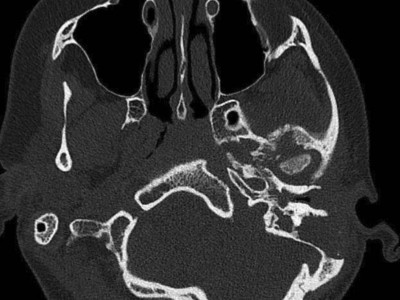

Was löst hier eine schwere Kiefergelenkzerstörung aus?

Weil die Schmerzen im linken Unterkiefer immer schlimmer werden, kommt die 26-jährige Patientin in die LMU-Klinik. Bereits seit fünf Jahren leidet sie unter wiederkehrenden Schmerzen im Unterkiefer. Anamnestisch hat alles angefangen mit einer Otitis media acuta.

Aufbau bei einer endoskopische Mittelohrchirurgie/© Mir-Salim P., Berlin, In-Ear-Kophörer/© diy13 / Stock.adobe.com (Symbolbild mit Fotomodell), CT des Felsenbeins bei Osteomyelitis der Schädelbasis/© Dewenter I.. et al. doi.org/10.1007/s00106-025-01649-6 unter CC-BY 4.0, Mikrobiom auf der Haut am Finger/© STEVE GSCHMEISSNER/SCIENCE PHOTO LIBRARY /Getty images / iStock, Otitis externa/© Dr. P. Marazzi / Science Photo Library (Symbolbild), Mann hält sich eine Hand ans Ohr/© herlanzer / stock.adobe.com (Symbolbild mit Fotomodell), Älterer Mann legt ein Hörgerät an/© VioletaStoimenova / Getty Images / iStock (Symbolbild mit Fotomodell), Kleinkind mit Cochleaimplantat/© satura86 / Getty Images / iStock (Symbolbild mit Fotomodell), Älterer Mann fasst sich ans Ohr/© Nes / Getty Images / iStock (Symbolbild mit Fotomodell), Ein Arzt bereitet das Hörscreening bei einer Frau vor/© kaisersosa67 / Getty Images / iStock (Symbolbild mit Fotomodell), Otoskopie bei einem jungen Kind/© SolStock / Getty Images / iStock (Symbolbild mit Fotomodellen), Hörgerät im Ohr einer älteren Person /© edwardolive / stock.adobe.com (Symbolbild mit Fotmodell), Frau mit schmerzverzerrtem Gesicht in Wohnzimmer/© fizkes / stock.adobe.com (Symbolbild mit Fotomodell), Mann erleidet Schwindel/© Tunatura / Getty Images / iStock (Symbolbild mit Fotomodell), Frau mit Kopfschmerzen/© MaximFesenko / Getty Images / iStock (Symbolbild mit Fotomodell), Eine ältere Frau riecht an einem Basilikumblatt/© Halfpoint / Stock.adobe.com (Symbolbild mit Fotomodell), Otoskopie in der Praxis/© RomanR / stock.adobe.com (Symbolbild mit Fotomodell), Person hält Medikamente/© fizkes / Stock.adobe.com (Symbolbild mit Fotomodell), Titel/© J. Hornung, Erlangen, Cholesterolgranulom im MRT/© Frederik F/ all rights reserved Springer Medizin Verlag GmbH, Tampanometrie bei einem Kind/© peakSTOCK / Getty Images / iStock (Symbolbild mit Fotomodell), Kleine Saktosalpinx rechts /© Universitätsklinikum Carl Gustav Carus, Dresden, Tympanometrie bei einer Frau/© Viacheslav Yakobchuk (Symbolbild mit Fotomodell), Hörgerät Modell/© Kaulitz S et al. / all rights reserved Springer Medizin Verlag GmbH, Eine Lehrende Person unterhält sich mit einem Kind mit Cochlea-Implantat/© vgajic / Getty Images / iStock (Symbolbild mit Fotomodell), Mann mit Zeichen einer Schwerhörigkeit/© Rido / stock.adobe.com, Computertomographie Felsenbein links /© Marti S et al. doi.org/10.1007/s00106-025-01602-7 unter CC-BY 4.0, Neugeborenen-Hörscreening/© isayildiz / Getty Images / iStock (Symbolbild mit Fotomodell), Eine Frau steckt sich die Finger in die Ohren zum Schutz vor Lärm/© apomares / Getty Images / iStock (Symbolbild mit Fotomodell), Atemwegsinfektionen/© (M) RFBSIP / stock.adobe.com / stock.adobe.com (Symbolbild mit Fotomodellen), Search Icon, HNO-Untersuchung beim Jungen/© adamkaz / Getty Images / iStock (Symbolbild mit Fotomodellen), Infusion/© georgeoprea9 / Getty Images / iStock